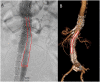

Purpose: Open surgical repair of type Ia endoleak after endovascular aortic aneurysm repair/sealing (EVAR/EVAS) is associated with significant perioperative mortality and morbidity. Current endovascular redo techniques face limitations, especially when the infrarenal landing zone is inadequate and the previous endograft is rigid and features a short or no main body. We present a novel concept for the treatment of type Ia endoleak using a custom-made branched device.

Technique: The 5-branch-device (Cook Medical, Bloomington, IN, USA) consists of a nitinol skeleton with branches, covered with a low-profile polyester fabric loaded in an 18F sheath. The device features a minimum of 2 proximal sealing stents and includes branches for renovisceral vessels as well as an additional 8 mm branch for the contralateral iliac limb. Implantation and sealing in the renovisceral vessels is carried out in standard fashion, using transfemoral and transaxillary access. Distal sealing is achieved by tapering the branched component into the ipsilateral iliac limb and using a bridging balloon-expandable or self-expandable stent-graft through the additional branch to the preexisting contralateral iliac limb.

Conclusion: Treatment of type Ia endoleak with a new custom-made device enables sufficient proximal seal while minimizing suprarenal aortic coverage and facilitates adequate component overlap. The low profile branched design accommodates implantation through the preexisting endograft and catheterization of target vessels.